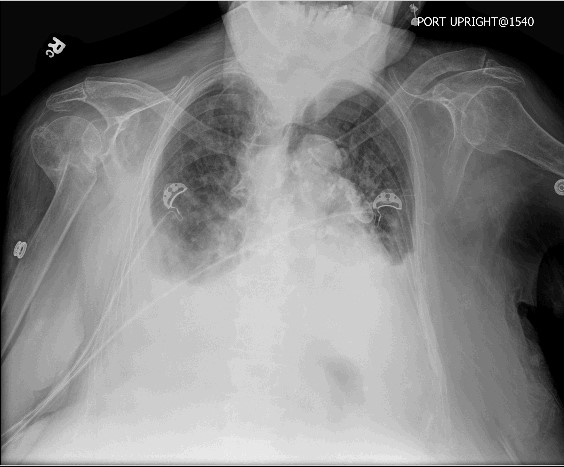

Laboratory analysis was only remarkable for a elevation of her creatinine to 1.8 mg/dL from a baseline value of1.3 mg/dL. The chest radiograph is shown below.